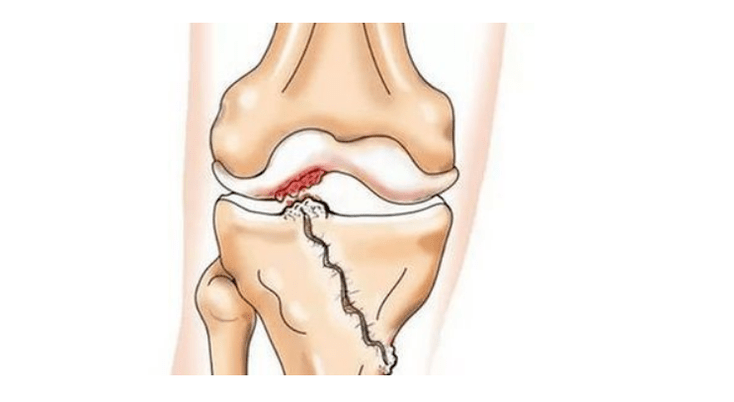

- verwondingen (fracturen, meniscus- en voorste kruisbandrupturen). Helaas leiden deze verwondingen bij iedereen, ongeacht de leeftijd, tot overmatige belasting van het kraakbeen. Een breuk van een deel van de botten bedekt met kraakbeen gaat gepaard met de vorming van een oneffenheid - een "stap". In dit gebied treedt tijdens het bewegen slijtage op en vormt zich artrose;

Bij artrose (osteoartrose) worden, naast de progressieve vernietiging van kraakbeen, verlies van de elasticiteit en schokabsorberende eigenschappen, botten geleidelijk bij het proces betrokken. Onder belasting verschijnen scherpe randen (exostoses), die ten onrechte als "zoutafzettingen" worden beschouwd - bij klassieke artrose vindt geen zoutafzetting plaats. Naarmate de artrose vordert, blijft het het kraakbeen ‘opeten’. Dan raakt het bot vervormd, vormen zich daar cysten, worden alle structuren van het gewricht aangetast en wordt het been gebogen.